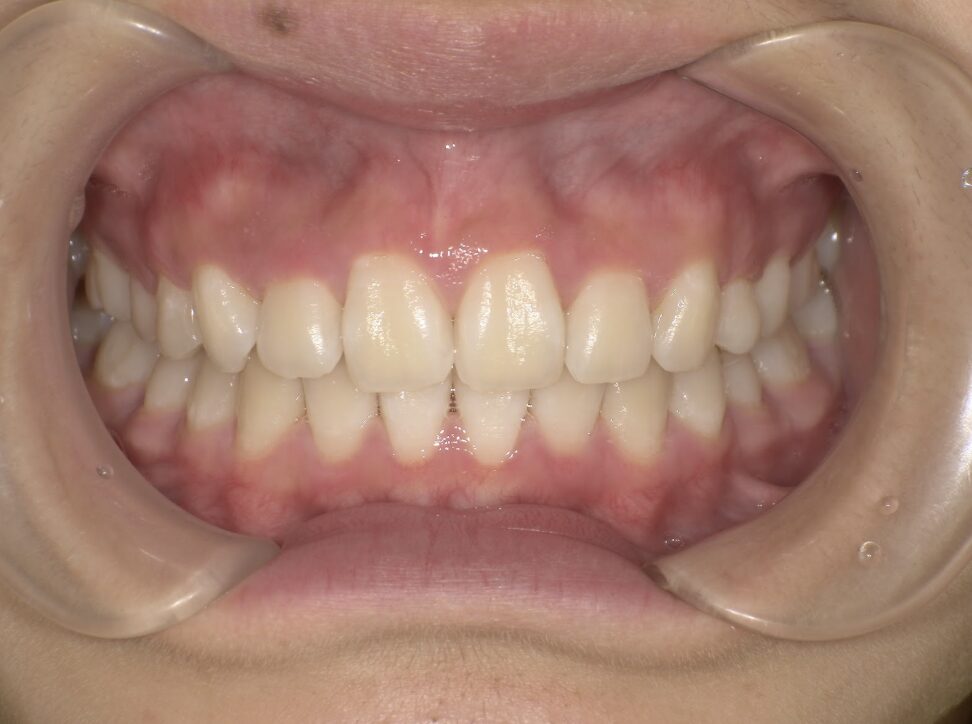

クロスバイト

BEFORE

治療前

ガタガタを主訴に当院を受診され、右上2番にクロスバイトを認めました。IPRを使用してマウスピース型矯正装置(インビザライン)を使用し改善を行いました。